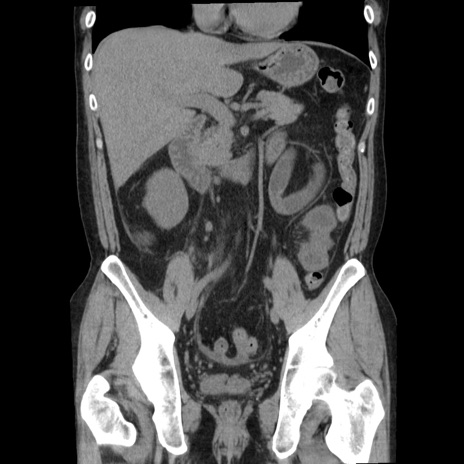

症例29(冠状断像)

【症例】40歳代男性

【現病歴】2日前から胃痛あり。徐々に周期的な激痛に変化した。本日になっても激痛があるため受診。

【身体所見】意識清明、BT 38-39℃台あり、腹部:膨満、やや硬、右下腹部に圧痛あり。

【データ】WBC 8500、CRP 23.26